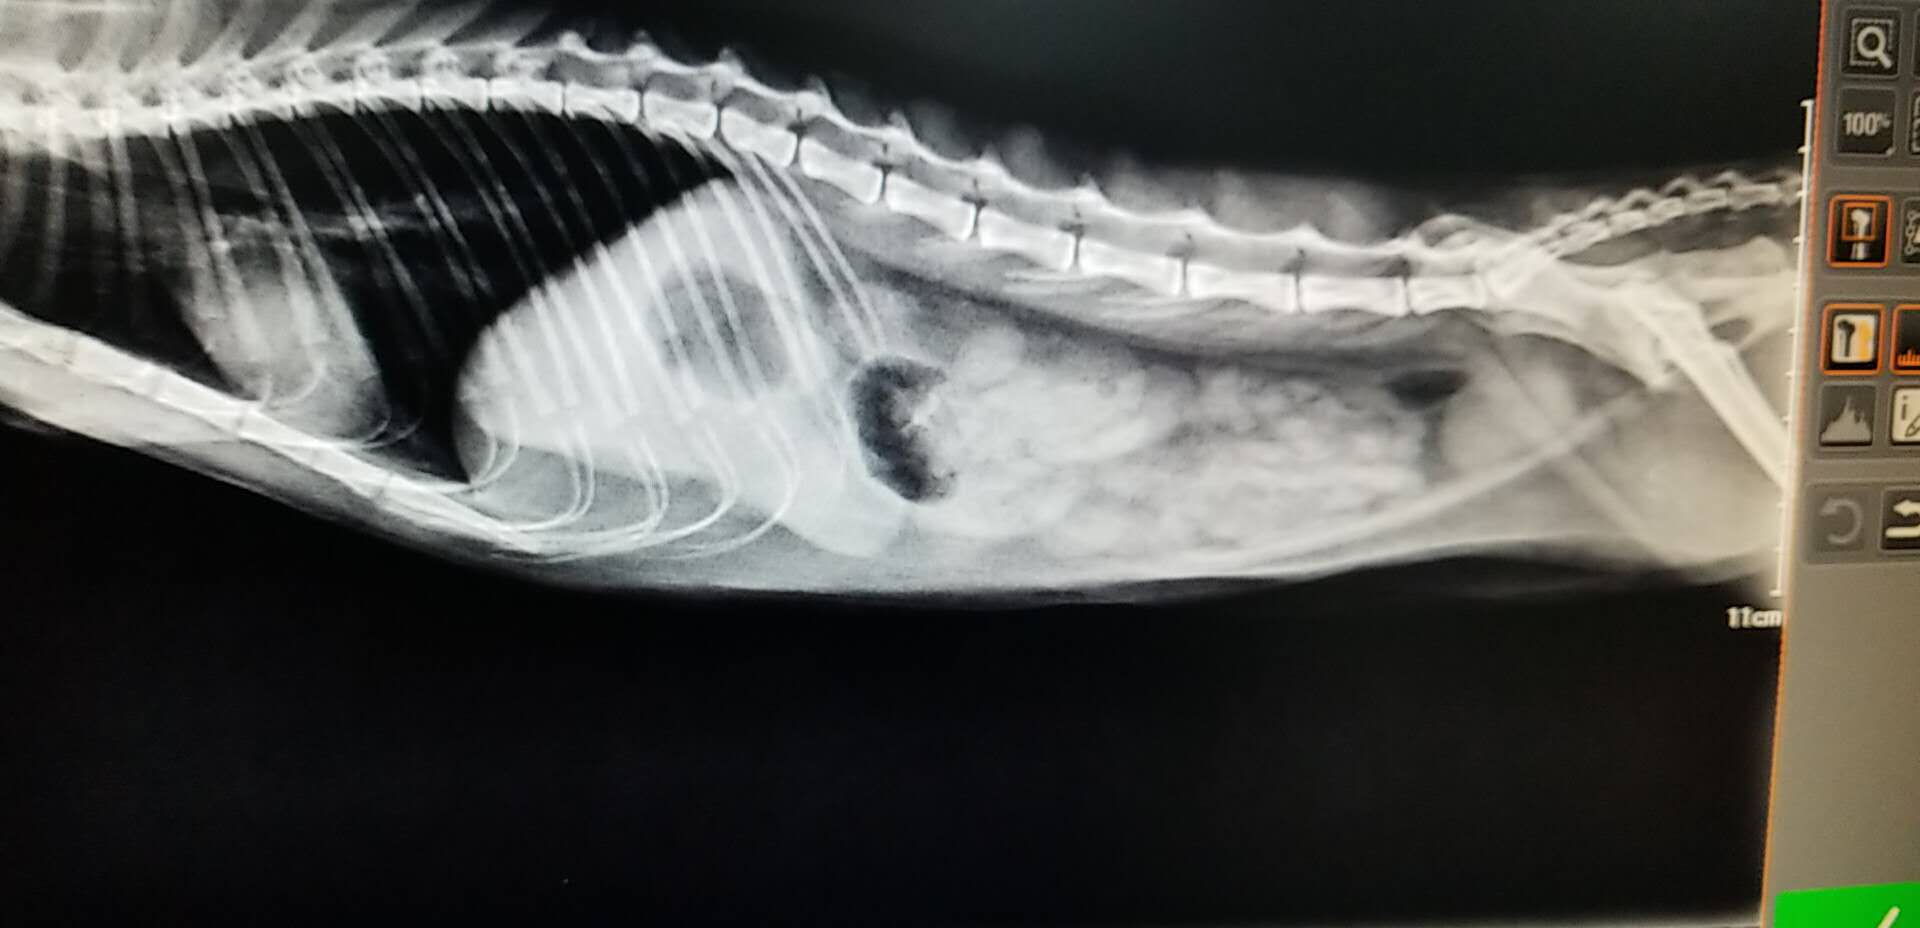

★血液以及影像学检查:血常规提示患猫存在轻度的脱水,生化检查未见明显异常。X-ray提示腹腔存在少量气体,肠腔未见明显异常增大。超声下,可见胃内存在大量的液体,肠腔大量液体,肠道不蠕动,在停止蠕动的肠道段前后扫查,未见明显的异物和肿块。

X-RAY

猫咪的肠梗阻诊断是需要结合生活史,病史,免疫史以及临床的检查(主要是影像学)相结合,进行一步步的排查才可以进行诊断的。X-RAY的检查可见肠管的扩张,会具有特征性的气体影像。站立位置,可见液体和气体间的水平线,阻塞部位下的肠管则是空虚的影像。肠道积液,肠道蠕动异常。血检主要是看患猫是否存在脱水以及长时间的肠梗阻有没有导致严重的并发症,例如:败血症等等。